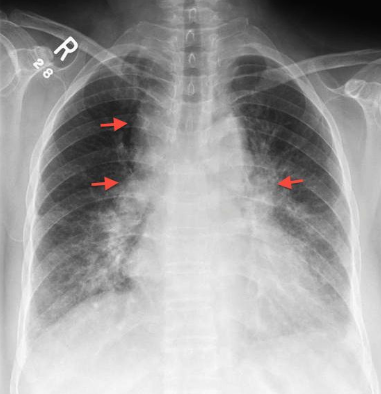

【肺門陰影増強の写真】

次の写真は両側の肺門陰影の増大が認められる。一般的に肺門陰影増大の原因としてはリンパ腺腫や静脈の拡張である。この写真では右の気管部の腫瘤が非常に特徴的で診断に有用。左右の肺門陰影の増強と右の気管支、および傍気管部の陰影。これはサルコイドーシスに見られる所見であり、”1-2-3サイン”とも呼ばれている。

肺門陰影増強(サルコイドーシス)の写真その2